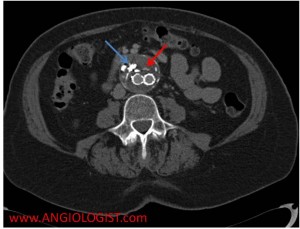

- Type II endoleak – Results from a blood vessel that is filling the original aneurysm sac around the graft. Three blood vessels that are commonly implicated in type II endoleak are lumbar arteries, accessory renal arteries and the inferior mesenteric artery. An important principle to understand regarding type II endoleaks is that there should always be two arteries visible entering the aneurysm sac – one artery is the one carrying blood to the sac and the other taking it out (otherwise the sac would always grow and rupture).

Two signs during imaging suggest an endoleak. The first is continued aneurysm expansion despite treatment. The second is extravasation of contrast material from within the artery (or graft) into the aneurysm sac. When this occurs the type of endoleak needs to be delineated. This is done by examining the endoleak location, looking for a blood vessel entering the aneurysm sac and making sure the stent is complete (without overt flaws in the stent). Another tip for proper CT imaging of endoleak is to use delayed images (typically at 70 seconds after contrast injection). At this time equilibrium has been achieved. A common mistake is mistaking calcifications and contrast extravasation on CT. Therefore a comparison of the contrast and non-contrast images should be made.